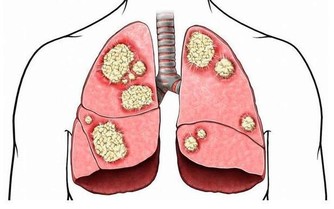

在某些情況下,手臂處的深靜脈血栓會分離出一部分隨血液流動,最終會進入肺部,誘發肺栓塞。

動脈栓塞是指血栓或血管中的異物阻礙了動脈血液流通,當栓塞到達手臂動脈時,

通常會引起手臂皮膚變色、手指冰冷異常,患者還會感覺上肢無力,或是直接喪失手臂的運動能力。